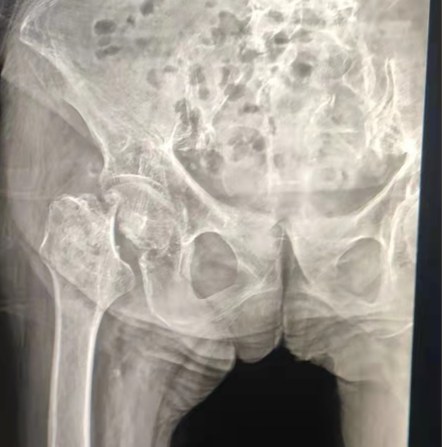

Case Sharing | 70-летний пациент, получивший полную замену тазобедренного сустава цементированной тазобедренной системой Lepu

Цементированная тазобедренная система:

Материалы сплава Ко-Кр-Мо

Высокая износостойкость

Большая механическая прочность

Дизайн плечевой резьбы

Легко установить, удерживать и регулировать угол

Полированная обработка поверхности

Для достижения отличного врастания кости Обеспечение стабильности ранней фиксации

12/14 Стандартный дизайн конуса

Proximal Mix Anatomy

Дизайн Коллекция Европа и США Особенности стебля

Дистальная обработка вырезывания Адге обеих сторон

Снижение давления в медуллярной полости